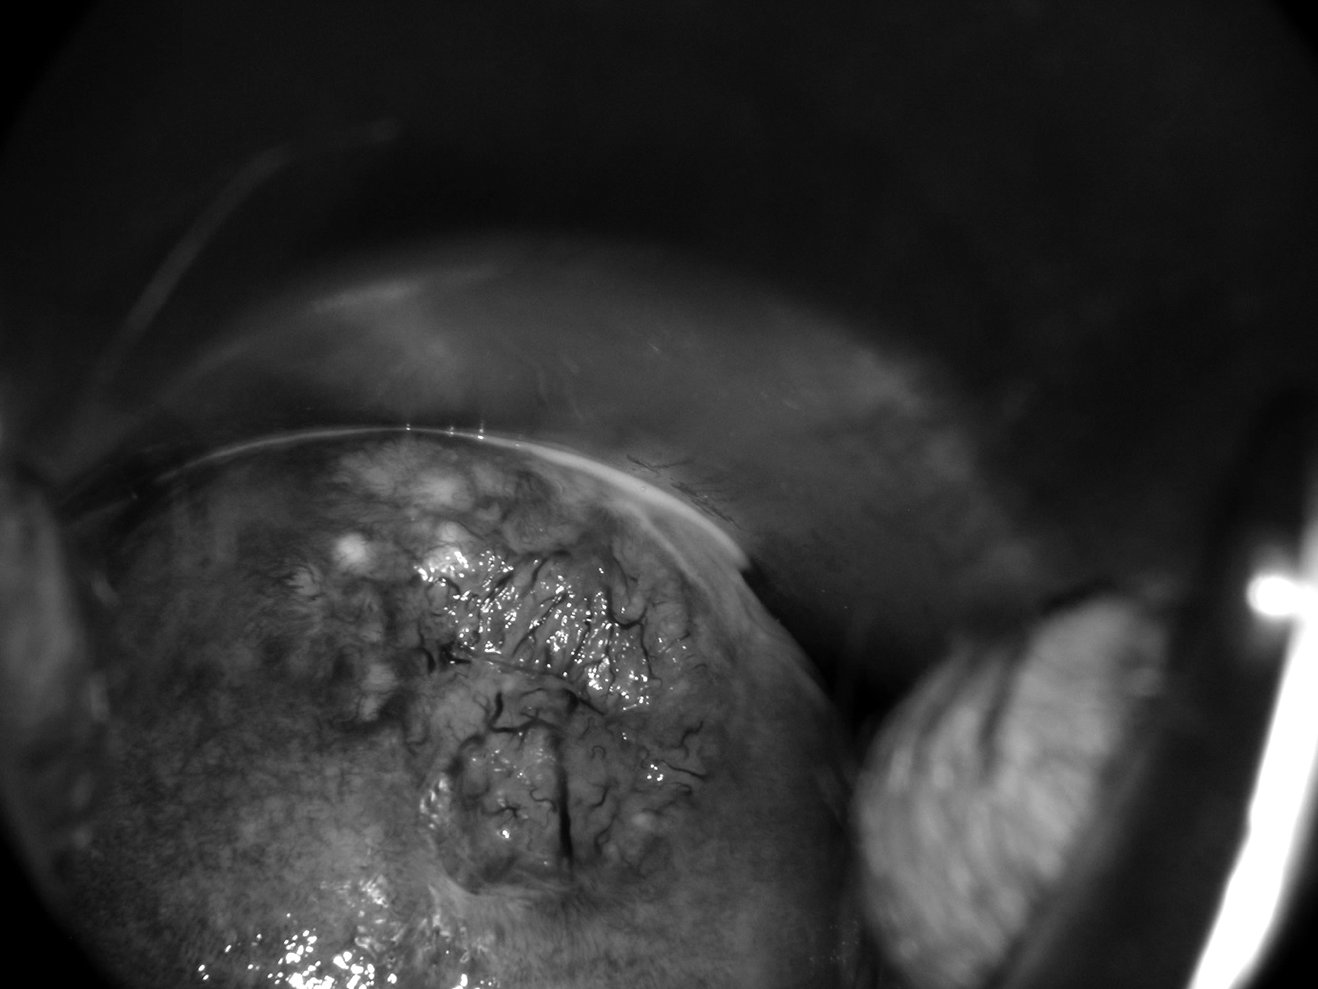

L’observation sans préparation qui commence au faible grossissement. À ce stade de l’examen, on peut utiliser le filtre vert pour l’observation des vaisseaux (figure 18.6).

Figure 18.6 Colposcopie sans préparation, mise en évidence de la vascularisation grâce à l’examen du col au filtre vert.